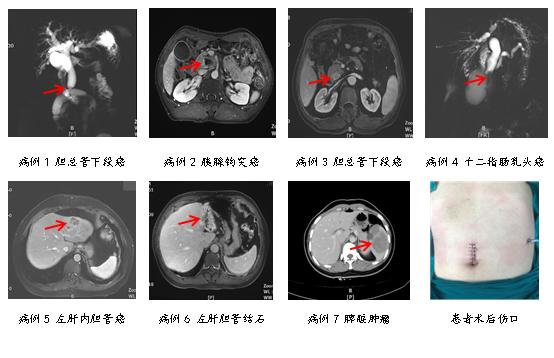

肝胆外一科团队在充分的技术储备、精密的术前规划及团队的密切协作下,2023年开始采用单孔3D腹腔镜技术,成功开展80余例单孔3D腹腔镜下胰十二指肠切除术、保留十二指肠胰头切除术、肝部分切除术、脾切除术及腹膜后肿瘤切除术,将我院腹腔镜微创技术提高到又一高度。